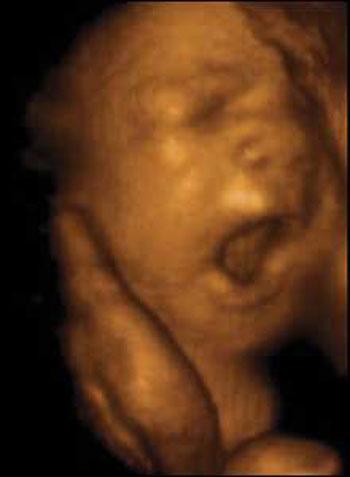

Ультразвуковые съёмки аборта на 12 неделе явно показывают: ребёнок чувствует боль, как любой из нас, и прекрасно понимает, что его хотят убить - он всеми силами старается отодвинуть от себя инструмент и широко раскрывает рот в безмолвном крике, когда у него отрывают сначала ноги, затем часть туловища…

Голову извлекают в последнюю очередь и лицо убитого ребёнка всегда искажено гримасой боли и ужаса. По этим кадрам видно, что практически нет разницы, убить ли 3-месячного ребёнка в утробе или отрезать руки -ноги -голову 5-летнему малышу. Без анестезии и в полном сознании.

- Фильм американского врача Бернарда Нэйтансона, названный «Безмолвный крик», показал всему миру, что такое аборт на сроке 11 недель беременности. Многие врачи и медсестры, посмотрев фильм, прекратили участвовать в абортах.

Это документальный фильм, и авторы рекомендуют соблюдать осторожность при его показе, поскольку некоторые кадры могут вызвать у человека психологический шок: безмолвный крик внутриутробного младенца, искаженное от боли лицо ребенка, погибающего на наших глазах...

Из закадрового текста к фильму: «Инструмент еще не коснулся ребенка, но он уже возбужден, его сердечные удары учащаются и достигают приблизительно 200 ударов в минуту. Вакуум-кюретка нащупывает ребенка, и он широко раскрывает рот в безмолвном крике».